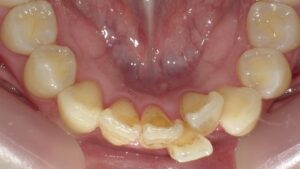

適切な根管充填が確認できる大臼歯の良好な根管治療例

大臼歯の根管治療は、根の本数が多く形態も複雑なため、細い枝分かれや湾曲を確実に清掃・消毒して緊密に封鎖する必要があります。そのため前歯や小臼歯に比べて難易度が高く、精密さと高度な技術が求められます。